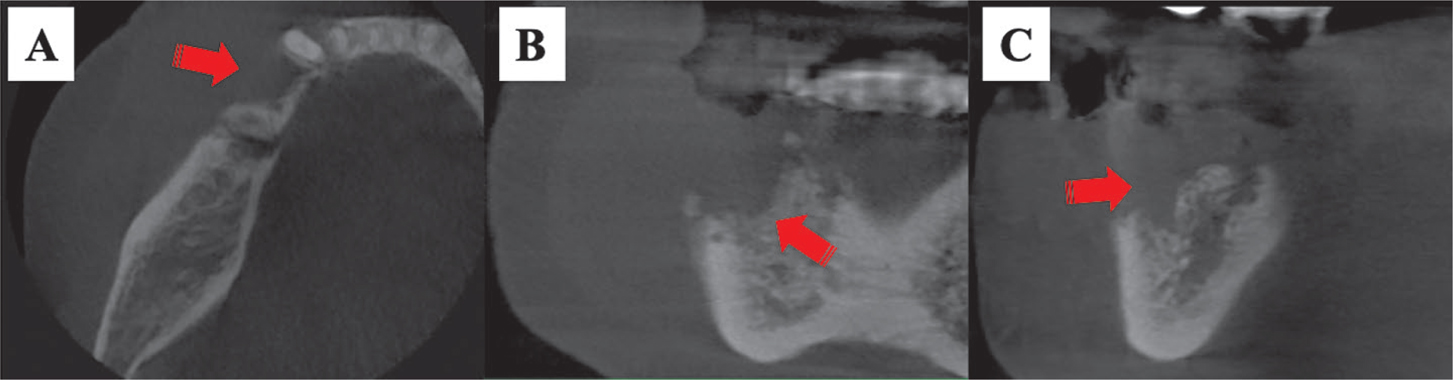

A dental CBCT is a specialized X-ray device used when conventional dental or facial X-rays are judged unsatisfactory for a comprehensive evaluation. With the help of this technology, physicians can get 3D images of bones, soft tissues, nerve networks, and teeth in a single scan. CBCT provides volumetric imaging of the bone structures in the craniofacial region at lower doses and costs than conventional CT. Even though CBCT imaging might not guarantee enough soft tissue contrast, it does offer precise details on the morphological characteristics and extent of lesions. Practitioners can also use dental CBCT to assess the probable existence and degree of osteomyelitis in the differential diagnosis of cysts, tumors, and ORNJ (74). Additionally, it is possible to evaluate lytic changes, cortical bone resorption, and surrounding structures when ORNJ is investigated using CBCT (8) (Figure 2). CBCT is essential for a precise diagnosis since it can reveal sclerotic regions, pathological fractures, and sequestrum. Osteomyelitis may be distinguished from ORNJ and MRONJ using CBCT with an accuracy rate of 90%. CBCT offers more information when describing necrotic zones than OPT. By demonstrating higher amounts of periosteal bone development in MRONJ than in ORNJ and cortical bone resorption rather than osteomyelitis in ORNJ, CBCT examination may also help distinguish the two disorders (86). CBCT can distinguish necrosis from other osteolysis cases that may be present (79). In summary, all these significant properties of CBCT make it a reliable method for the discriminative diagnosis of bone disorders (86).

Fig 2

Figure 2. Cone beam computed tomography. Images showing extensive bone resorption and sequestration of osteoradionecrosis in the right mandibular premolar region (red arrows). A: axial; B: coronal; C: sagittal.